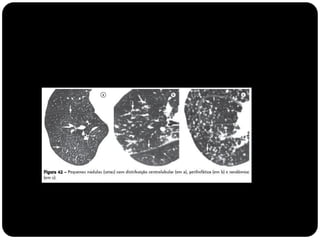

 Figura do “ComputedTomography of the lung...”(Baert 2007)

Lóbulo pulmonar secundário

Menor porção do pulmão, ainda circundada por um septo de

tecido conjuntivo;

Composto por 3 a 5 bronquíolos terminais (3 a 12*)

Identificado naTCAR tanto em estados normais quanto

patológicos;

Revestidos por septos interlobulares que contém as tributárias das

veias periféricas e dos vasos linfáticos;

 Ácinos pulmonares: porção do pulmão distal a um

bronquíolo terminal e consiste dos bronquíolos respiratórios,

dos ductos alveolares, dos sacos alveolares e dos alvéolos;